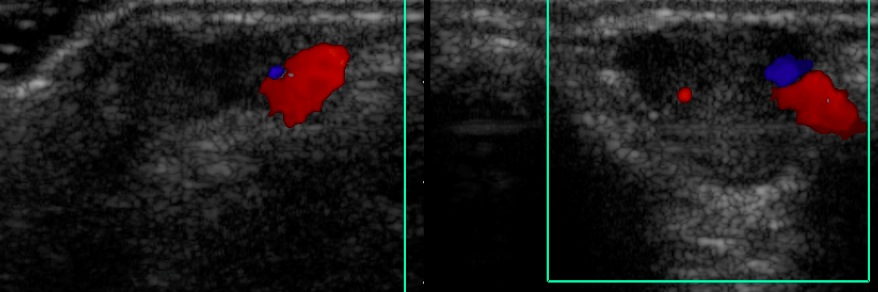

Figure 1 for case Venous malformation ( RID3337 )

Figure 1